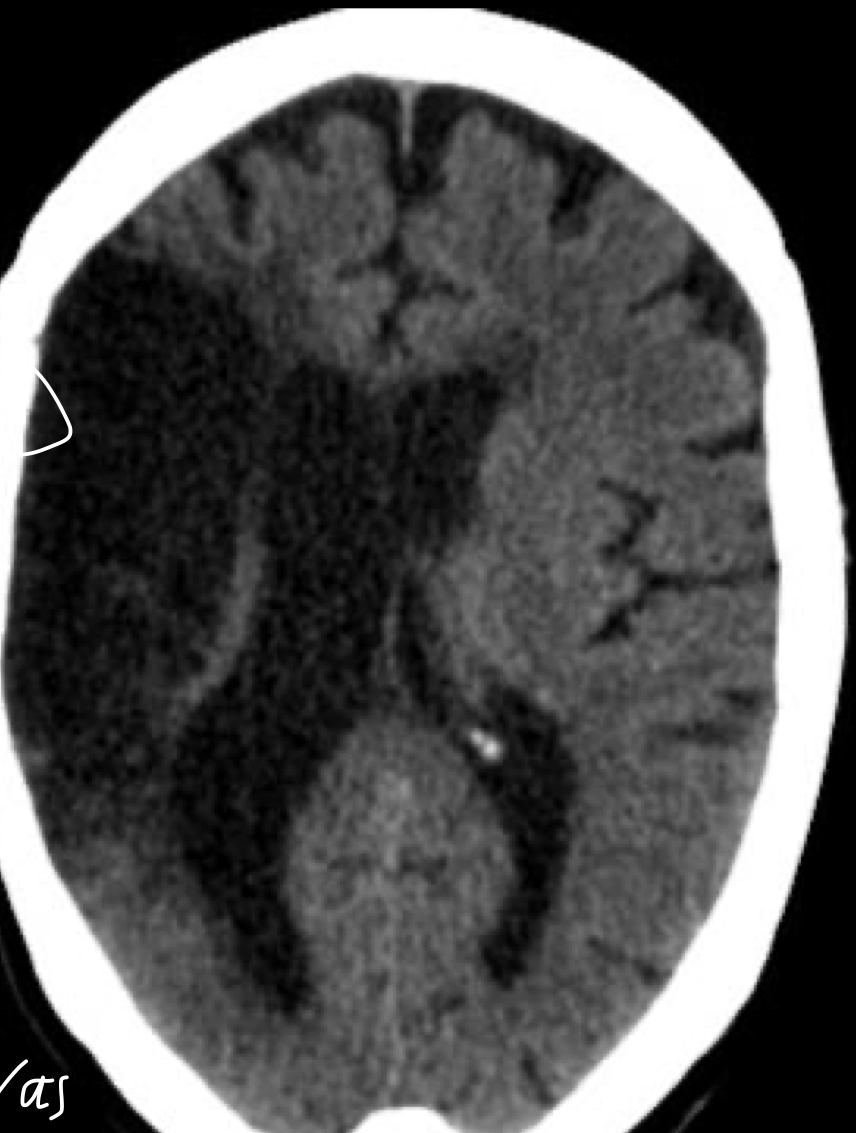

Q

Que es?

A

ECV isquemico agudo